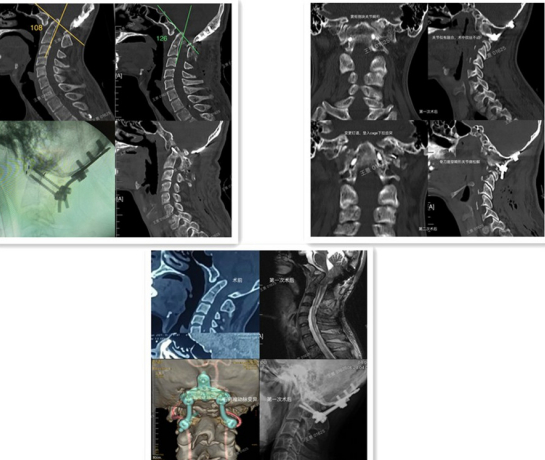

王景为患者完善相关检查,明确诊断为寰枢椎不可复性脱位、Chari I型畸形、脊髓受压、枕颈融合术后、椎动脉变异,手术治疗风险和难度极高。经过详细术前准备,在全麻下为患者实施寰枢椎不可复性脱位后路复位固定融合翻修手术。术中暴露颅底及椎体骨性结构,拆除失效的内固定装置。在显微镜辅助下,松解双侧侧块关节,置入椎间融合器解除脊髓压迫,并行后方植骨融合。术后患者的齿突斜坡角由术前的108°增加到126°,脊髓压迫症状明显改善,术后5天康复出院。